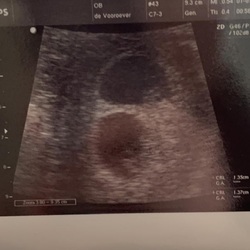

Hier ook zwanger van een tweeling! Eeneiig. Pas bij de derde echo bleek dat het er twee zijn, daarvoor hadden ze dit niet gezien! Heel bizar. Daarna in een achtbaan geraakt. Kreeg heel heftige pijn. Bleek om een dubbel gedraaide eierstok te gaan, dus moest met spoed worden geopereerd. Met de baby鈥檚 was gelukkig steeds alles goed! Alle risico鈥檚 maken me onzeker, maar ik probeer te genieten.